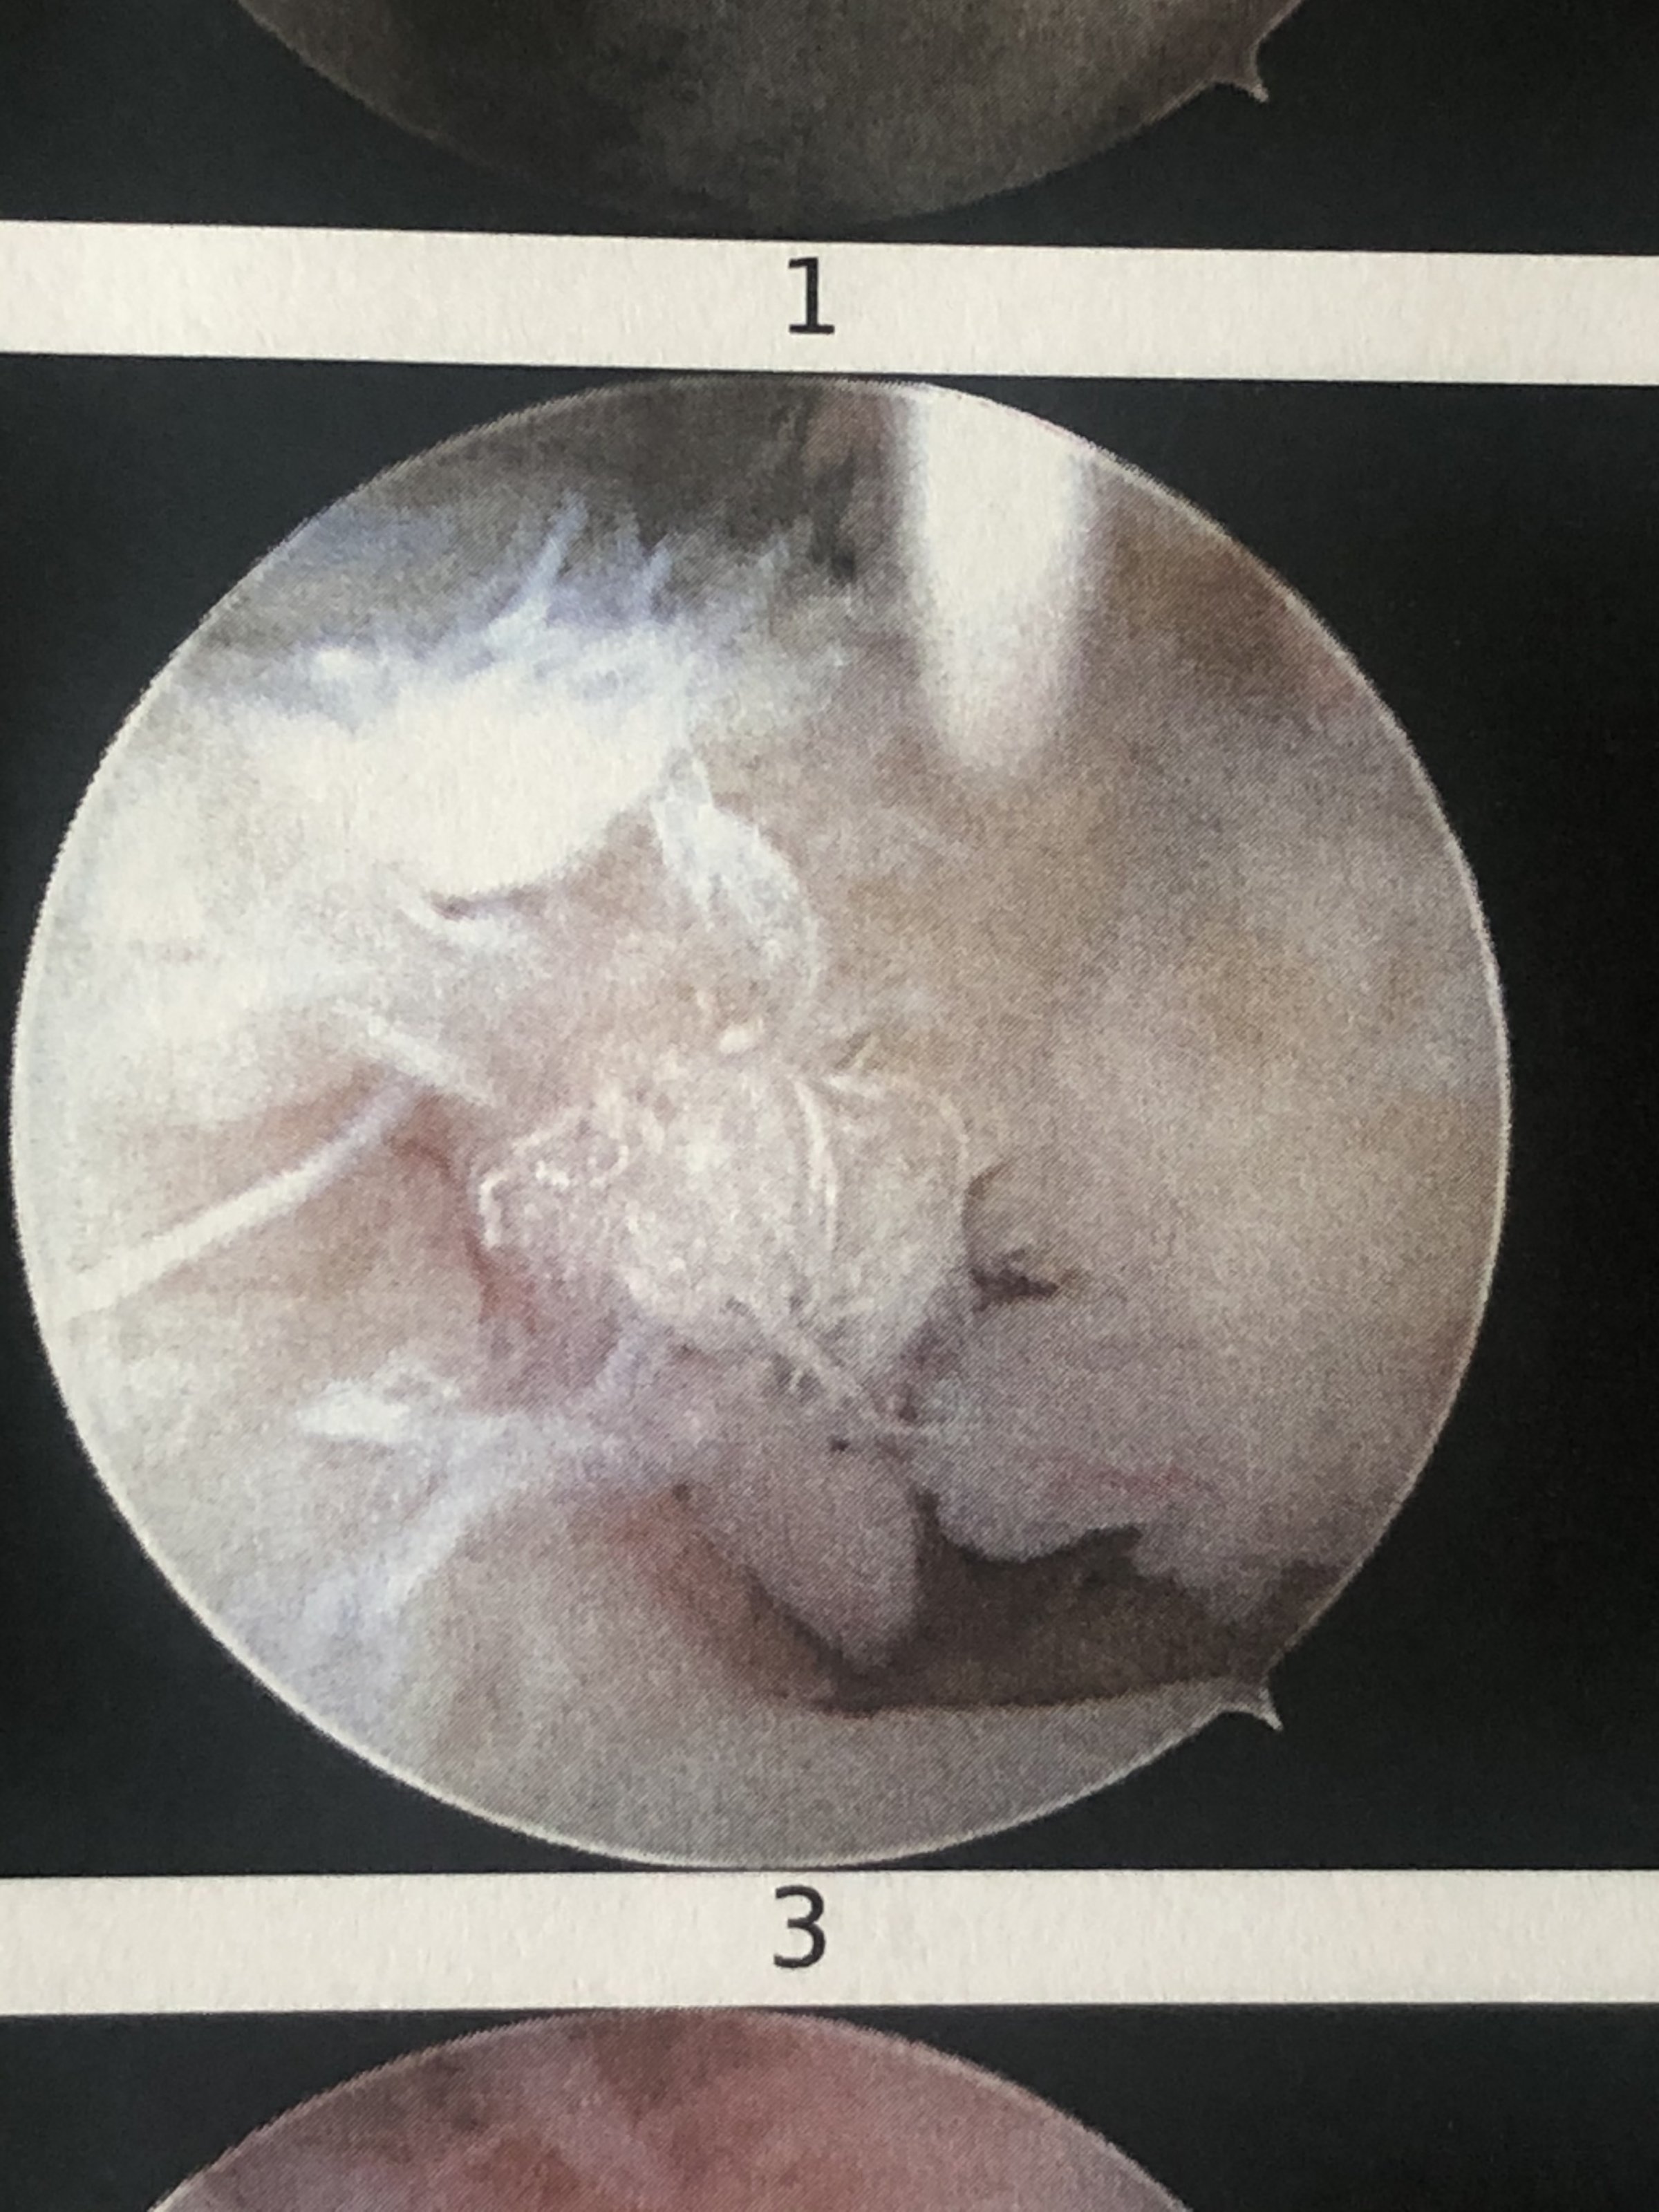

U.a. wurde diese zerfledderte Bizeps Sehne facioniert und woanders wieder mit Ankern befestigt. Die kompletten Bilderserien erspare ich euch

Anhang anzeigen 349443

Vereinfacht zusammengefasst: hat unter Belastung/Gewalteinwirkung (ohne Fremdverschulden) nicht gehaltenWas hast Du denn gemacht, dass das so aussieht?